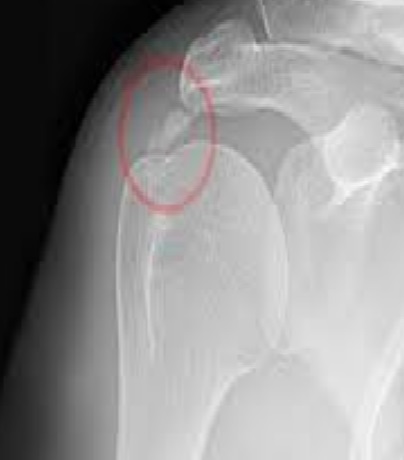

석회성 힘줄염은 말 그대로 어깨 힘줄에 석회(칼슘)가 침착되어 염증을 일으키는 질환이에요. 아직까지 정확한 원인은 밝혀지지 않았지만, 주로 힘줄의 퇴행성 변화나 미세한 손상, 혈류 감소 등이 원인으로 지목되고 있습니다. 30~50대 연령층에서 비교적 흔하게 나타나는데, 특히 어깨를 많이 사용하는 직업이나 반복적인 운동을 하는 분들에게 더 잘 생긴다고 해요. 꼭 나이가 많아야 생기는 건 아니라는 거죠.

석회성 힘줄염의 가장 특징적인 증상은 뭐니 뭐니 해도 극심한 통증이에요. 특히 통증이 갑자기 시작되는 경우가 많고, 통증 때문에 팔을 움직이는 것이 힘들어집니다. 통증의 시기와 강도에 따라 보통 3단계로 나누어 설명하곤 해요.